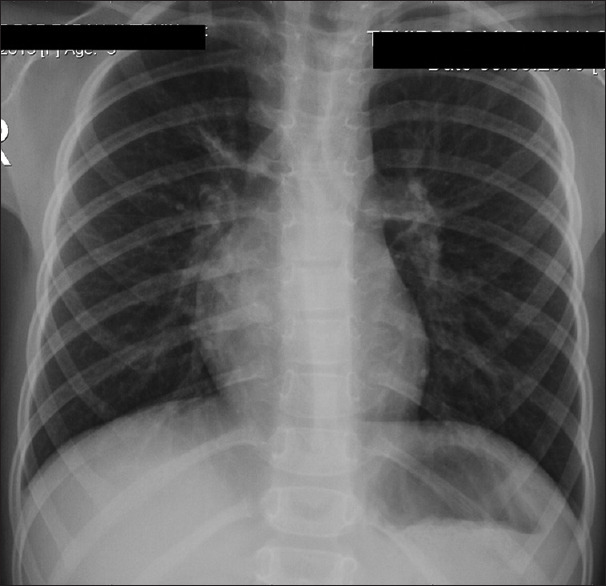

特发性脊柱侧凸(IS)通常与Chiari畸形(CM)和脊髓空洞相关,这些疾病被认为有一个共同的潜在原因:寰枢椎不稳定。寰枢稳定最近成为一种新的治疗选择。一名4岁女孩,表现为进行性脊柱侧凸(Cobb角28.6°)、颈部疼痛、CM和脊髓空洞。患者被诊断为寰枢中心或轴向不稳定,并接受C1-C2固定。术后,患者颈部疼痛明显缓解。随访显示进行性鼻窦缩小,x光显示Cobb角在18个月内下降至21°。本病例强调了寰枢椎稳定在IS合并CM和脊髓空洞的患者中阻止脊柱侧凸进展的潜力。与传统的多节段稳定不同,C1-C2固定提供了一种微创方法,并保留了生长年龄患者的脊柱活动能力。IS合并CM和脊髓空洞的病例应考虑寰枢椎不稳定。寰枢椎单独稳定可提供有效的治疗,并具有良好的临床和放射学结果。

Idiopathic scoliosis (IS) is frequently associated with Chiari malformation (CM) and syringomyelia, conditions thought to share a common underlying cause: Atlantoaxial instability. Atlantoaxial stabilization has recently emerged as a novel treatment option. A 4-year-old girl presented with progressive scoliosis (Cobb angle of 28.6°), neck pain, CM, and syringomyelia. The patient was diagnosed with central or axial atlantoaxial instability and underwent C1-C2 fixation. Postoperatively, she experienced significant relief from neck pain. Follow-ups demonstrated progressive syrinx reduction, while X-rays revealed a Cobb angle decrease to 21° in 18 months. This case highlights the potential of atlantoaxial stabilization to halt scoliosis progression in IS patients with CM and syringomyelia. Unlike traditional multisegmental stabilization, C1-C2 fixation offers a minimally invasive approach and preserves spinal mobility in growth-age patients. Atlantoaxial instability should be considered in IS cases with CM and syringomyelia. Atlantoaxial stabilization alone may provide effective treatment with favorable clinical and radiological outcomes.